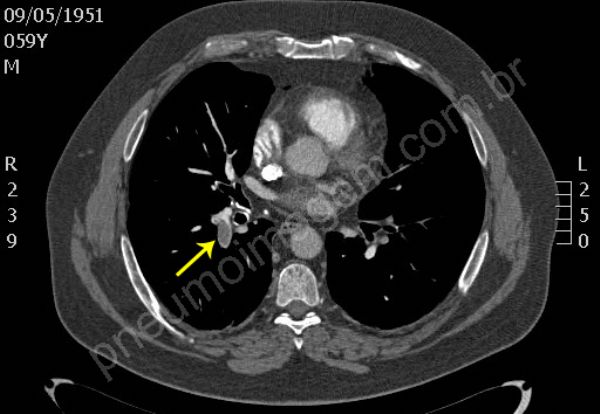

Tromboembolia pulmonar (TEP). Na sequência tomográfica observam-se trombos localizados no tronco da artéria pulmonar e nos principais ramos segmentares à esquerda. Os trombos na bifurcação do tronco pulmonar à direita estendem-se para ramos segmentares do lobo superior, para a interlobar descendente e ramos segmentares do lobo médio. O paciente apresentava também trombose venosa profunda (TVP) na veia femural esquerda, fator de risco importante para TEP. Chaves: tromboembolismo, embolia pulmonar.

Pulmonary thromboembolism (PTE). In tomographic sequence are observed thrombi located in the main pulmonary artery and major segmentary branches left. Thrombi in the bifurcation of the pulmonary trunk right extend to segmentary branches of the upper lobe, extend to descending interlobar and segmentary branches of the middle lobe. The patient also presented deep vein thrombosis (DVT) in the left femoral vein, an important risk factor for PE. Keys: pulmonary embolism (PE).